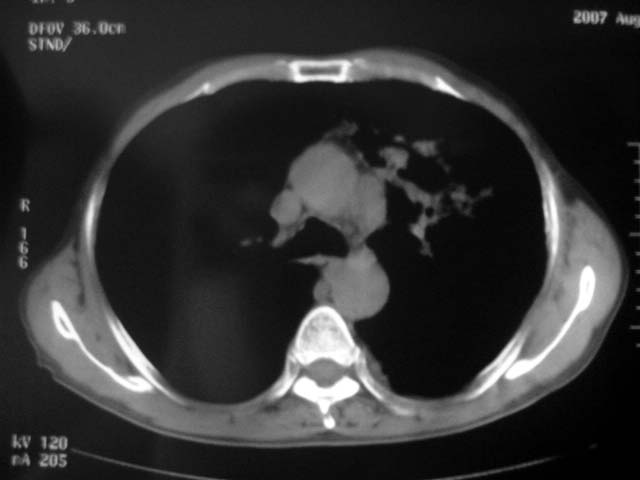

以下是引用zjzjr在2007-9-4 17:00:00的发言:[br]双上肺继发型结核伴左上肺空洞形成.慢性支气管炎伴肺气肿.

以下是引用liuzheng_9326在2007-9-4 16:23:00的发言:[br]痰检未见结核菌, 治疗后症状好转。图像符合陈旧性结核伴感染。